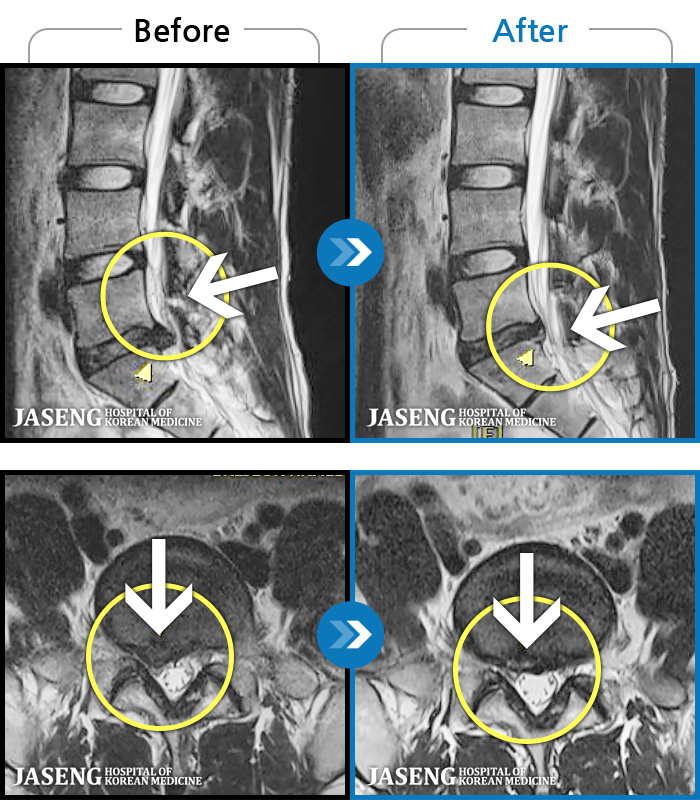

MRI ġ

1,299 MRI ũ ʸ Ȯϼ.